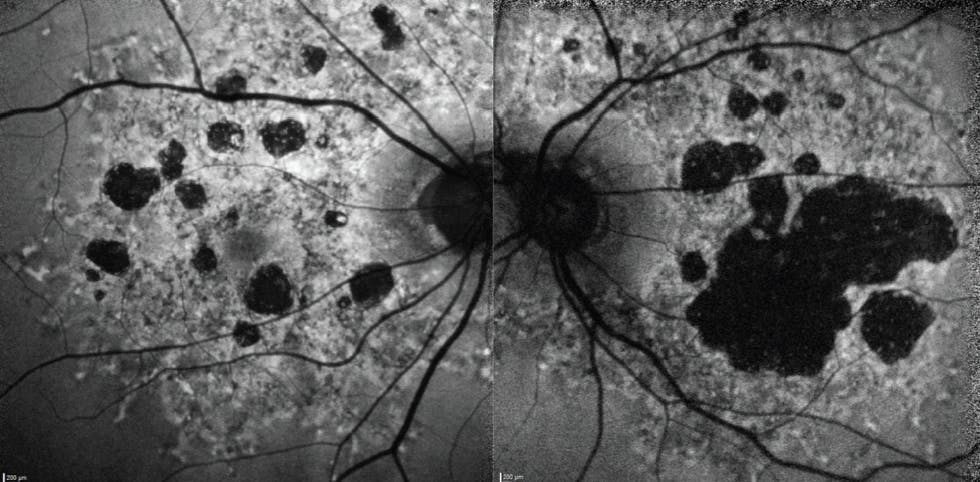

I performed fundus autofluorescence (FAF) imaging on presentation (Figure 1). Her left eye, which is her worse eye, showed extensive GA lesions, while her right eye showed multifocal, medium-sized lesions. Optical coherence tomography (OCT) of the right eye showed evidence of limited hypertransmission (Figure 2) whereas the left eye showed significant hypertransmission (Figure 3).

Figure 1. FAF imaging revealed extensive bilateral GA lesions. The patient’s right eye, which was her better-seeing eye, had medium-sized multifocal lesions, while her left eye had a large central lesion.